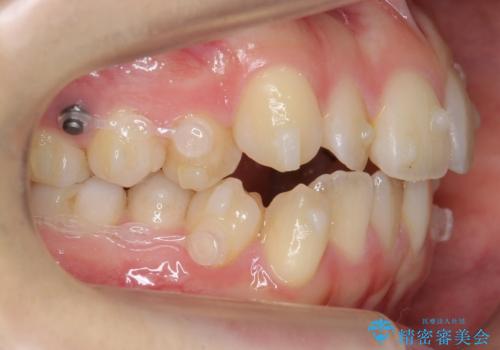

下の八重歯 歯を抜かずに インビザライン治療

- 歯並びのがたつきを主訴に来院。

抜歯してワイヤー矯正という選択肢も提案しましたが、マウスピース矯正で、歯を抜かずに並べてほしいとのことでした。

スペースを確保するために、歯をわずかに削る処置、奥歯を後ろに下げる処置(インプラント矯正)を行っています。

途中患者様のご都合で治療を中断していたため、長くかかっていますが、実質2年程度で終わる内容でした。